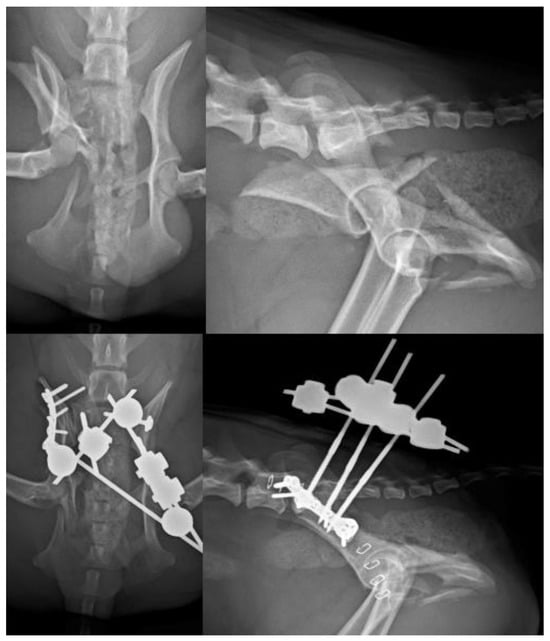

Figure 8. (Top left): VD view of a patient with fracture of the right ilium and of the right sacral articular process, and a left sacroiliac luxation. (Top right): Lateral projection of the same patient. (Bottom left): A combination of a type C EF and a plate have been used to stabilize the fractures. Note the lag screw for the left sacroiliac luxation. (Bottom right): Lateral projection of the same patient.